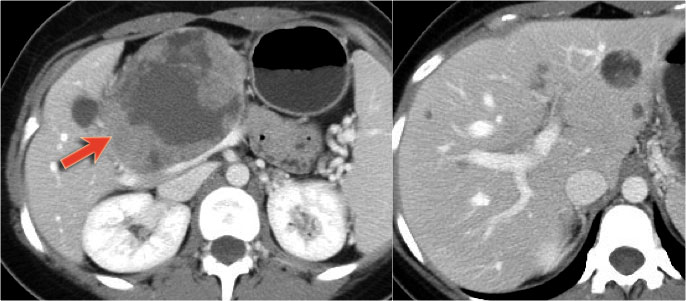

CT-images of a 61 year old woman with weight loss.

There is a large mass in the body of the pancreas that is hypervascular, unlike an adenocarcinoma, with some cystic or necrotic parts.

CT-image of a neuroendocrine tumor with central necrosis.

Sometimes this can simulate a cystic component.

Notice the peripheral enhancement.